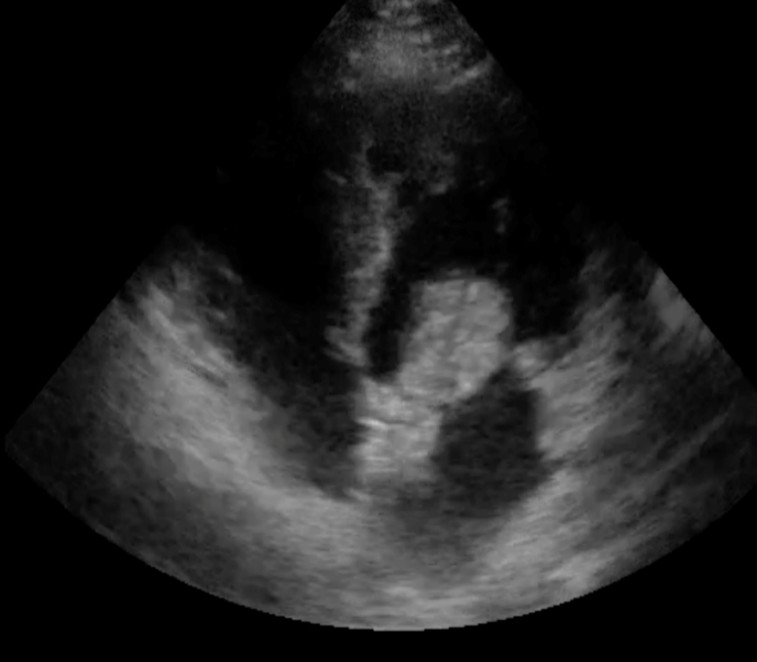

The echocardiogram report dated 29.01.2026 indicates the following findings:

- Large LA myxoma: A large myxoma (benign cardiac tumor) in the left atrium.